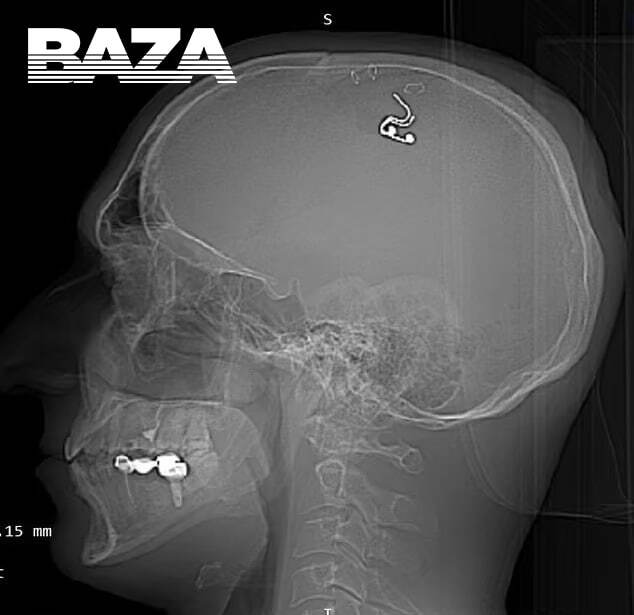

Картинка: Baza

40-летний Михаил Радуга — исследователь осознанных сновидений из Новосибирска. Недавно он решил сделать то, чего не удалось даже Илону Маску: чипировать собственный мозг, чтобы управлять снами. Правда, официального разрешения на это добиться невозможно, поэтому Михаилу пришлось проводить трепанацию самостоятельно — дрелью и скрепками в домашних условиях.

К операции исследователь готовится основательно: он часами смотрел видео на «Ютубе» о работе нейрохирургов и тренировался на головах мёртвых баранов. В итоге Михаилу удалось просверлить себе затылок и вживить в кору мозга электроды — это, по словам Радуги, уже дало первые результаты в сновидениях.

17 мая я это сделал. Операция заняла четыре часа — у меня есть полное видео. Там видно, как я вскрываю сухожильный шлем, сверлю отверстие в черепе, трепанацию делаю, под твёрдую мозговую оболочку устанавливаю электроды, провожу электрическую стимуляцию и зашиваю. Около литра крови потерял. Вот после этого я ещё проработал десять часов, как обычно. Потому что ты не можешь уснуть после операции. Я просто принял душ и работал дальше дома.

Сейчас мне их удалили. Правда, осталось, отверстие в голове — его расширили нейрохирурги, так как электроды стали врастать. Прошло три или четыре недели. Сейчас я восстанавливаюсь и дальше работаю. Всё хорошо.

40-летний Михаил Радуга сделал себе трепанацию прямо дома в Алматы, куда недавно переехал. Ради этого он часами изучал на «Ютубе» видео о работе нейрохирургов и даже попрактиковался на пяти овцах. Затем Михаил обзавёлся дрелью в хозяйственном магазине и приступил к делу: он просверлил себе голову, фиксируя кожу скрепками, и вживил в мозг электрод. По словам экспериментатора, во время операции он чудом выжил, потеряв около литра крови из-за нехватки хирургического опыта.